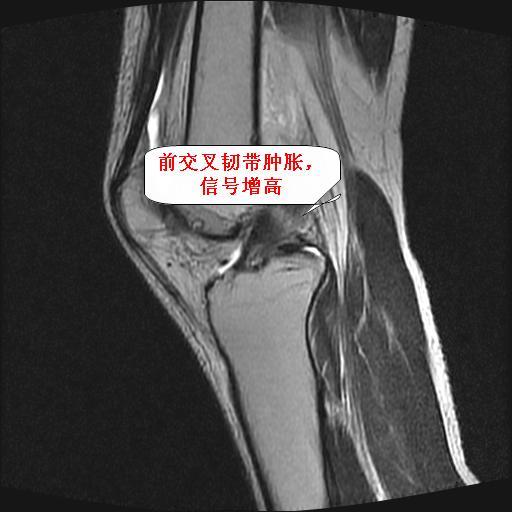

1、前交叉韧带撕裂;

前交叉韧带撕裂,关节腔积液.

半月板1-2级损伤   前交叉韧带撕裂伤   关节腔少量积液  诸骨未见新鲜外伤性改变

前交叉韧带撕裂,关节腔积液,支持!

半月板1-2级损伤   前交叉韧带撕裂伤   关节腔少量积液

2、前交叉韧带撕裂;

内侧副韧带撕裂及关节腔积液是肯定的,但是前交叉撕裂确定吗?会不会有容积效应的因素,因为前一张前交叉显示清楚,连续性良好,且较光滑。请问楼主有关节镜支持吗?我们医院也经常有这样的患者,但苦于没有关节镜,而无法对照、证实(除非完全断裂),出现了不同的诊断结果只能毫无意义的争论。

1、前交叉韧、内侧副韧带撕裂;

2、前交叉韧带撕裂